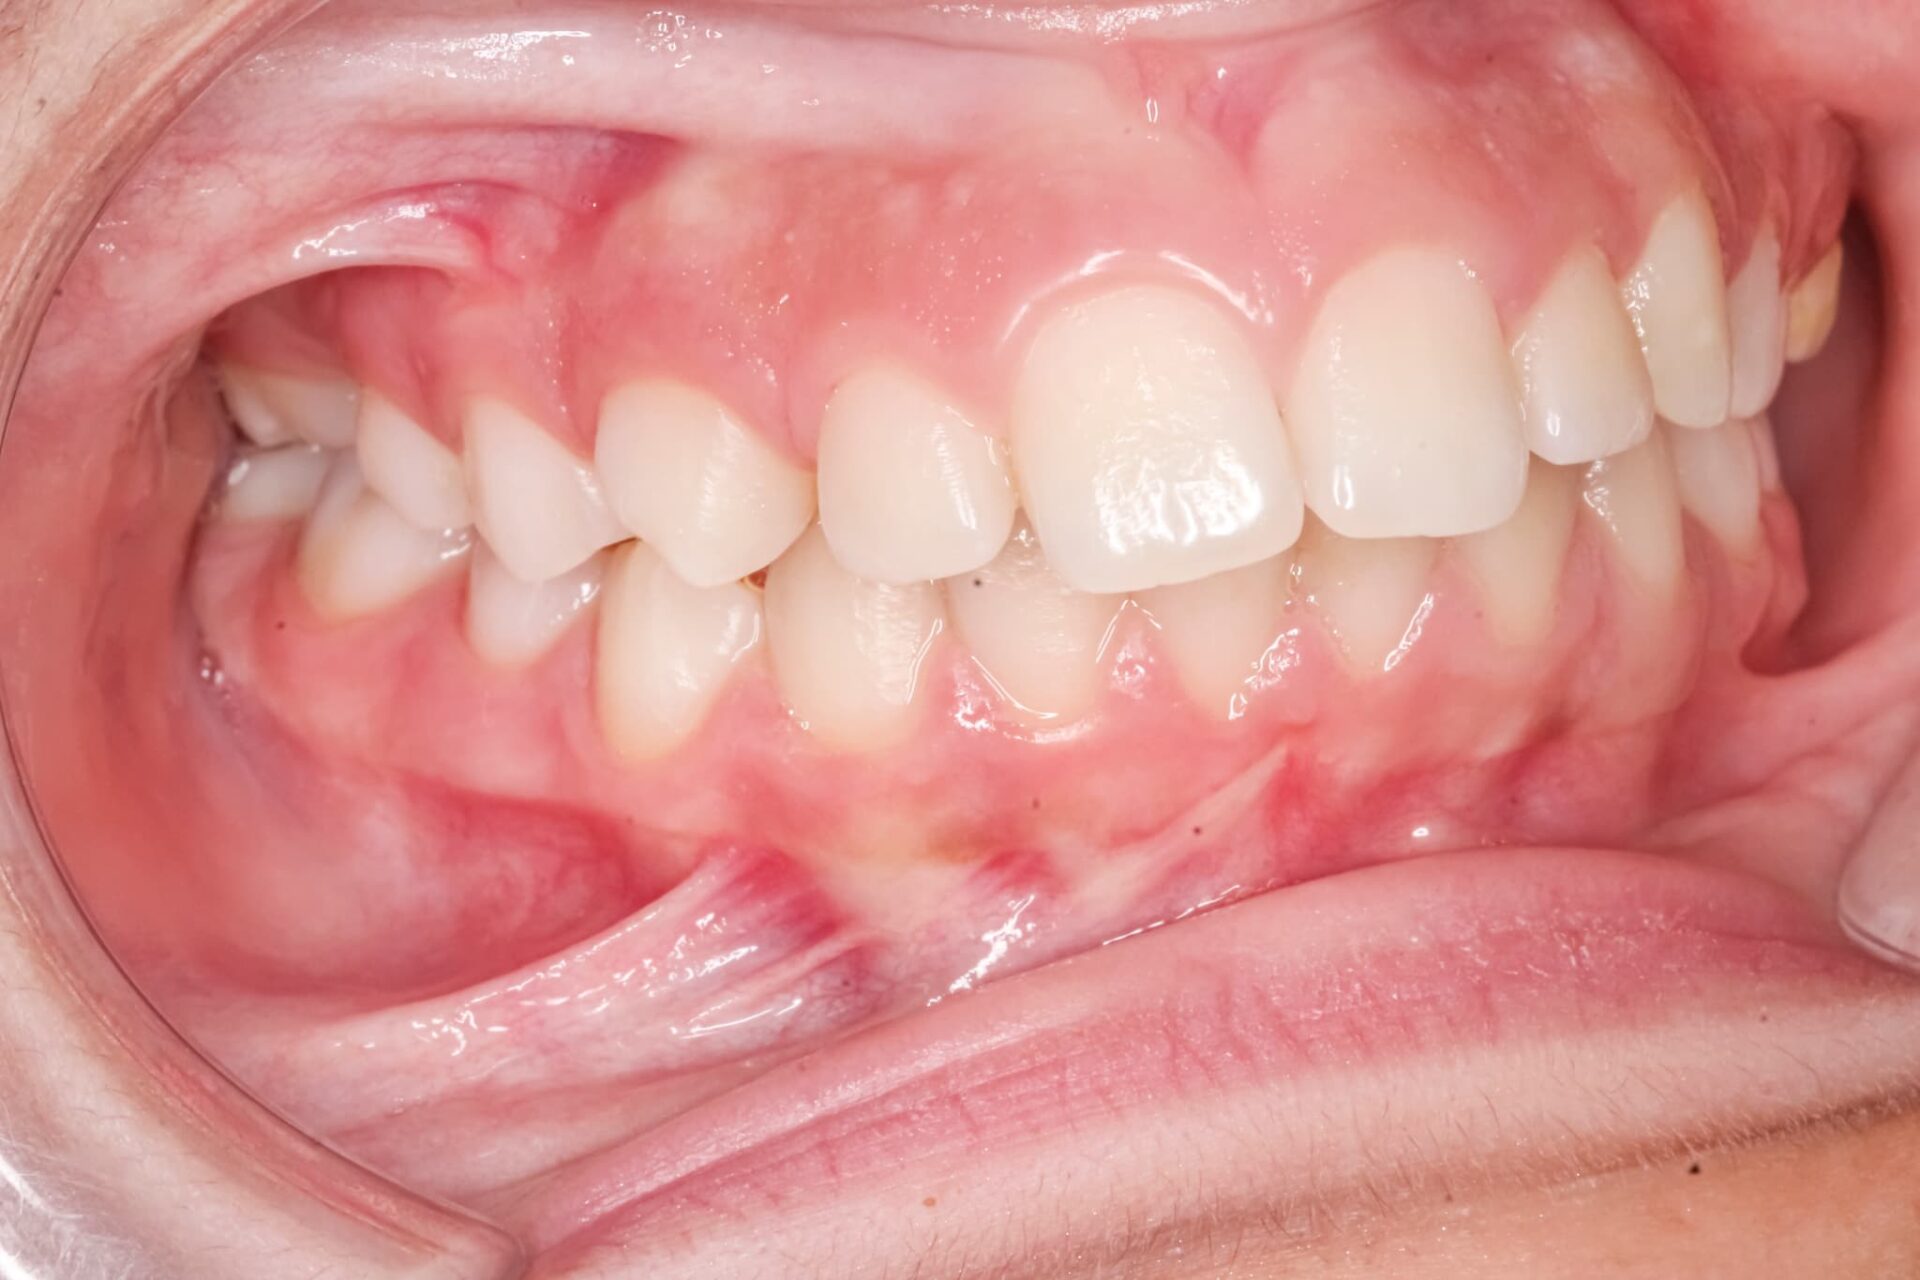

上の前歯は、下の前歯より2〜3mmほど前に出ているのが理想的な状態です。

出っ歯は専門的には上顎前突と呼ばれる不正咬合の一つで、上の前歯や上顎そのものがこれを大きく超えて前方に突出しています。横から顔を見たときに上唇が前へ出て見える、口を閉じにくい、前歯で食べ物を噛み切りにくいといった症状が見られ、口呼吸の原因になることもあります。